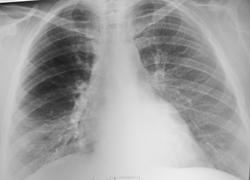

Случай №1 Молодой человек, 20 лет, лыжник. Был направлен терапевтом для исключения пневмонии. Беспокоит кашель и небольшие подъёмы температуры. Слева обратил внимание на очаги, размером до 8-10 мм на интактном лёгочном поле. Возможно это сосуды. Подозрение упало на ТБС. В заключении написал консультацию фтизиатра.

Случай №1. Пусть спокойно бегает на лыжах и дальше.

Случай №1. ИМХО.: Пневмония в н/доле справа